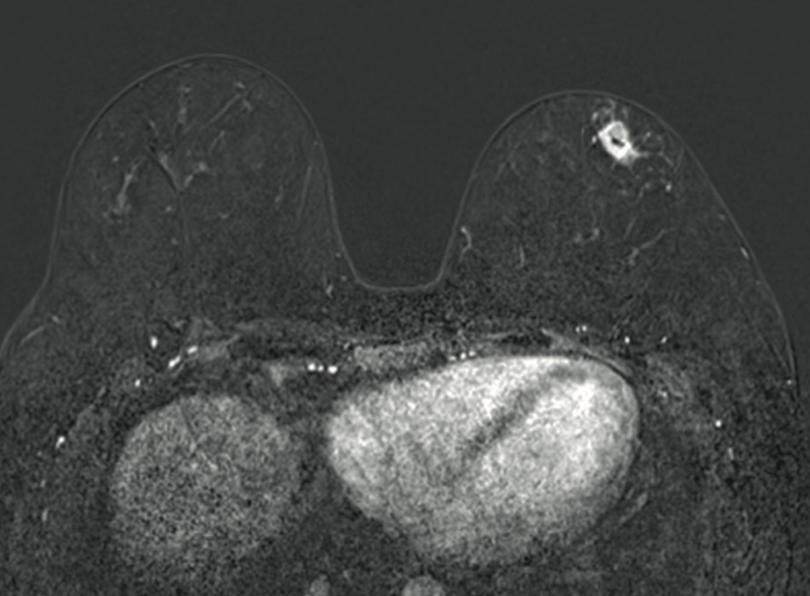

Imágenes y Cirugía

|

Diego Soto V, Cristian Marín O, Sebastián Morales Z